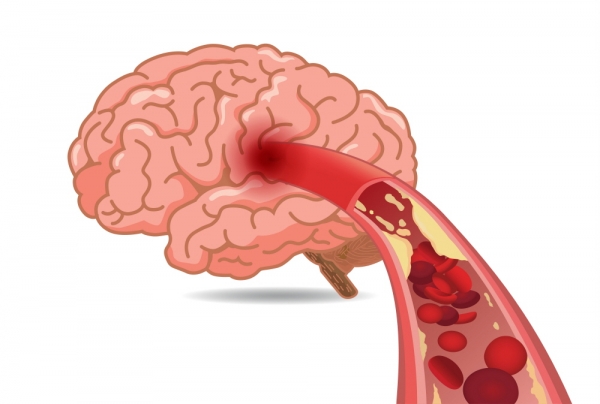

뇌경색 초기증상에 대하므로 살펴볼게요니다. 뇌에도 혈관이 있어서 피가 흐르고 있어요. 뇌에 있는 혈관이 막혀서 뇌의 일부가 손상되는 것을 뇌경색이라고 말해요. 뇌혈관이 막혀 뇌가 손상되면 장애가 발생할수 도 있으므로 뇌 연관 질환은 각별한 주의가 필요해요.

뇌경색의 주된 이유가 되는 것은 혈전이지요. 혈전이란 혈관 속에 피가 굳어진 덩어리를 얘기하는데 이것이 혈관을 막는 것이 뇌경색에 큰 영향을 줄 수 있습니다. 평균적으로 많이 발생하는 연령대는 5~60대이지요. 뇌경색은 양쪽 뇌에 모두 나타나는는 것이 아니라 주로 한쪽 뇌에만 발생하지만, 주로 한쪽 팔다리가 마비되었다거나 얼굴 근육이 굳어버리기도 해요. 그렇기에 뇌경색 초기증상이 발생한다면 민첩하게 대응를 해야 하겠습니다.